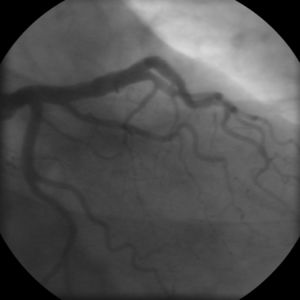

Coronary angiogram of a man

Coronary angiogram of a woman